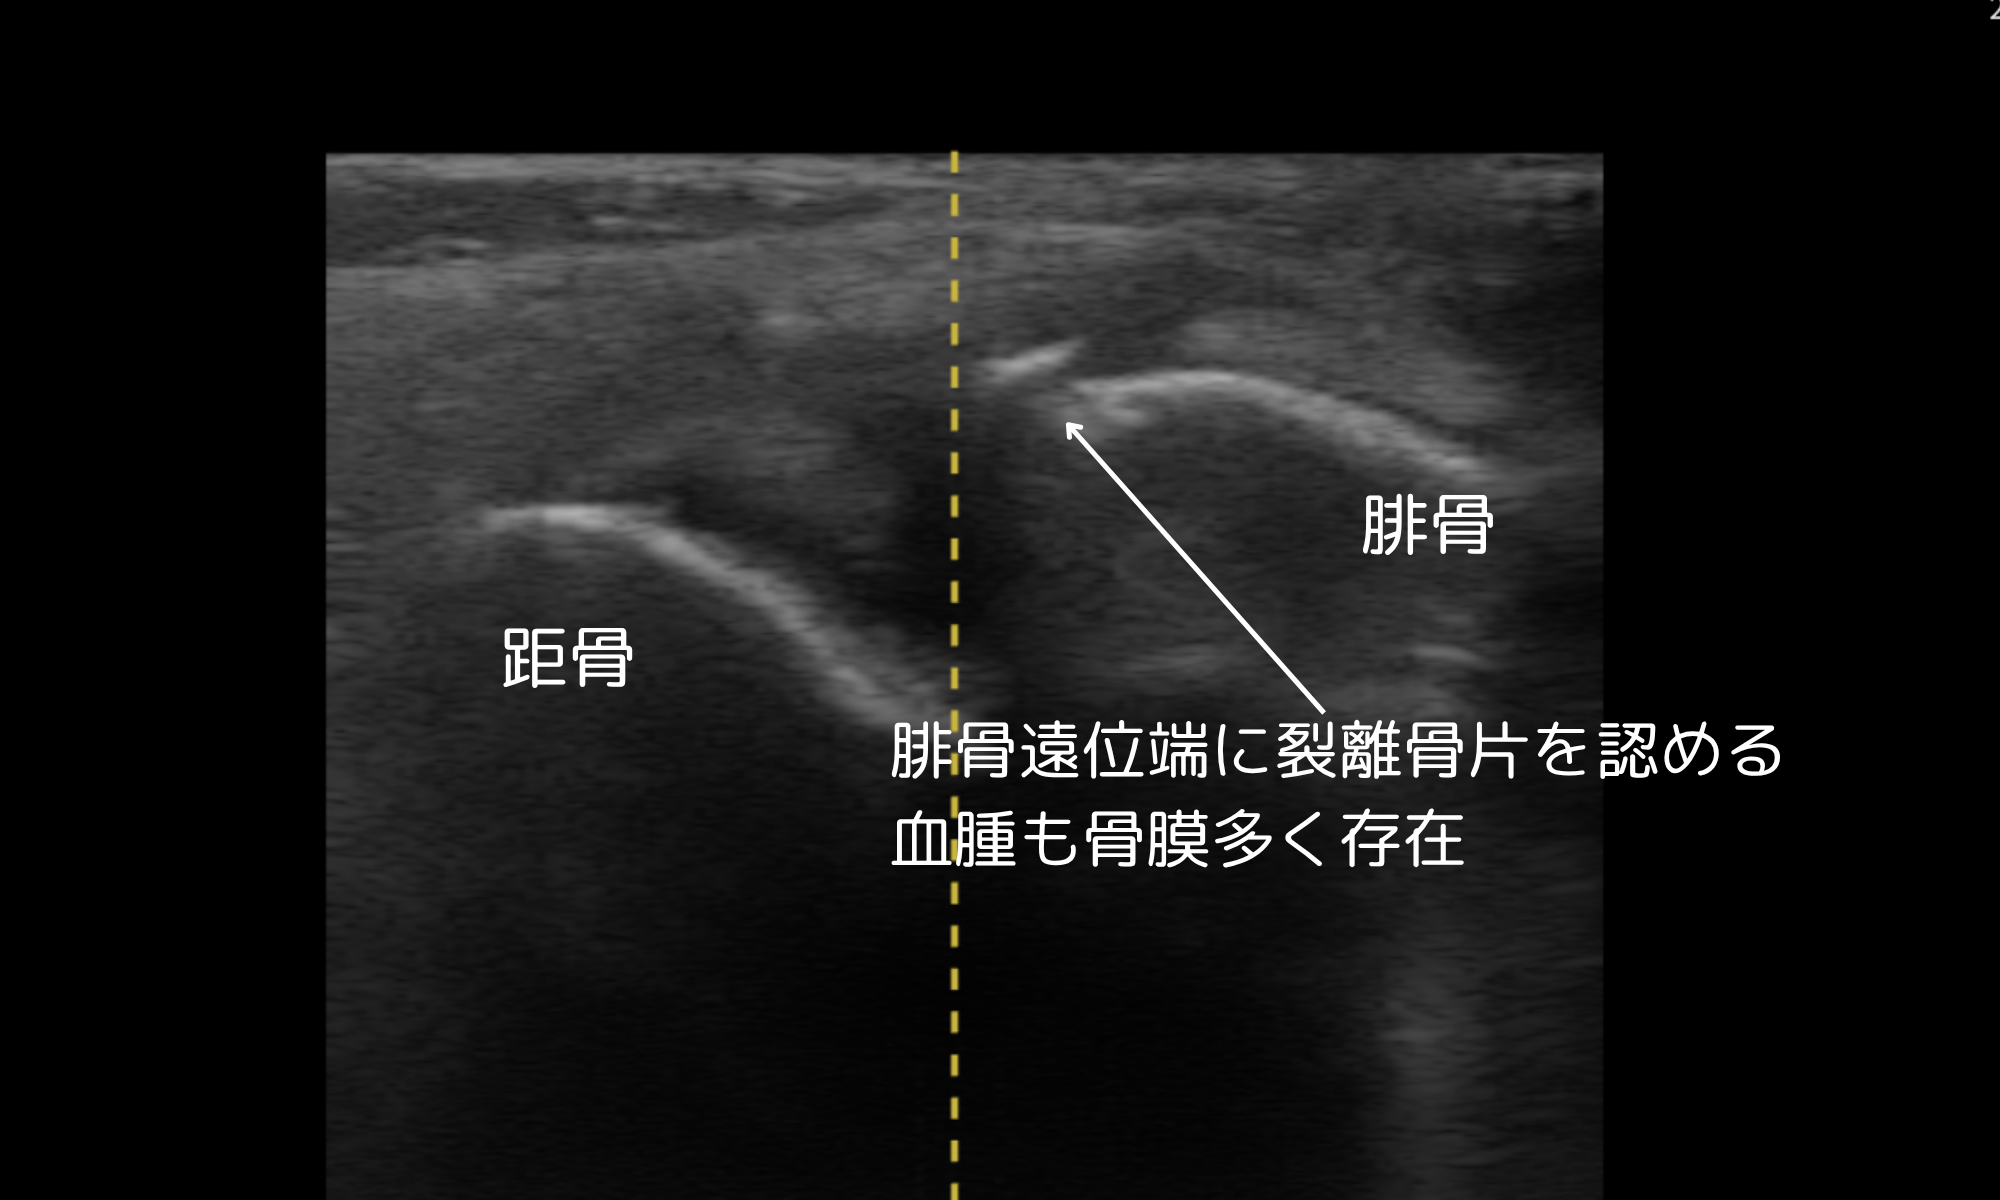

エコー観察による診断

腓骨遠位端に裂離した骨片を確認。

小児に多い裂離骨折であり、レントゲンでは見逃されることもあるタイプです。